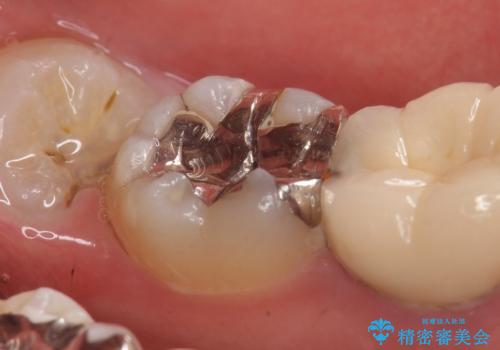

- 右下7の銀歯を白くしたいといらっしゃった方の症例です。

銀歯及び虫歯を除去後、セラミックインレーで修復を行いました。